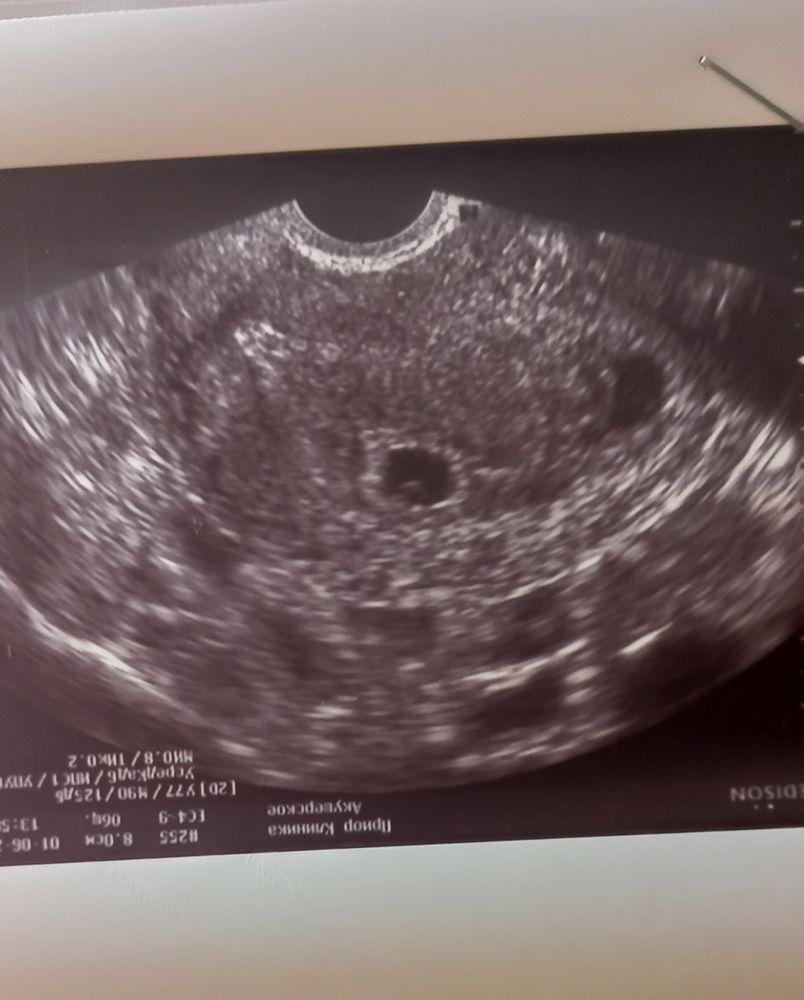

21 дпп знакомство с Пузыриком

Наконец-то, сгорая от нетерпения, я познакомилась с Пузыриком🤩 Он на месте- это хорошо.

А вот на дне матки есть ретрохориальная гематома- это плохо😪